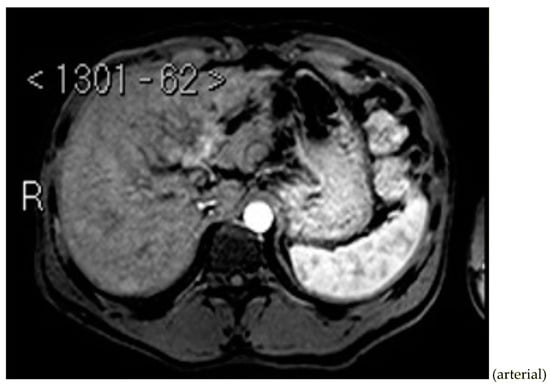

Subsequently, an upper-abdomen Computed Tomography (CT) scan and liver Magnetic Resonance Imaging (MRI) were performed (Figure 1, Figure 2, Figure 3, Figure 4, Figure 5, Figure 6 and Figure 7).

Figure 1.

CT arterial phase.

A mass of 1.8 cm was detected within the biliary branch for the third hepatic segment, characterized by nodular impregnation in the arterial phase and irregular and partial washout in the portal venous phase. These findings were compatible with a heterologous lesion, although it was not possible to perform a diagnosis among HCC, intrahepatic CCA or other pathological lesions.